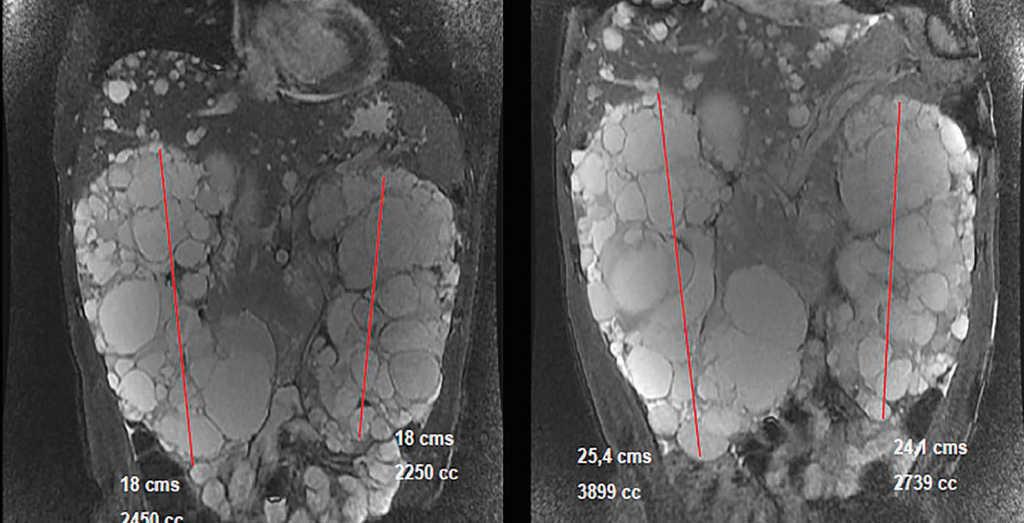

In March 2011, he began treatment with 40mg adalimumab (Humira®) every 15 days. At that time he had: haemoglobin (Hb) 12.4g/dl, creatinine (Cr) 2.3mg/dl, estimated glomerular filtration rate (eGFR) (according to Modification of Diet in Renal Disease) 34ml/min/1.73m2, proteinuria 10mg/dl. In September 2011 he had: Cr 3.24mg/dl, eGFR MDRD 23ml/min/1.73m2, proteinuria 1.78g/24h (Figure 1). Treatment was discontinued in January 2012 because the patient developed polyneuropathy and purpura. In February 2012 a nuclear magnetic resonance (NMR) displayed a right kidney of 18cm (volume of 2450ml) and a left kidney of 18cm (2250ml). In April 2012 the patient began a course of 50mg Golimumab (Simponi®) every five weeks. Six doses were administered and it was discontinued in September 2012 when the patient complained of a notable increase in his abdominal diameter and an umbilical hernia, which was directly related to the administration of the drug. A final dose was administered in December 2012. In March 2013, another NMR displayed a right kidney of 25.4cm with a volume of 3899ml and a left kidney of 24.1cm with a volume of 2739ml (Figure 2) and a slight increase in a much smaller amount of hepatic cysts.

Figure 2. Image comparing kidney size in the nuclear magnetic resonances of 2012 (left) and 2013 (right).